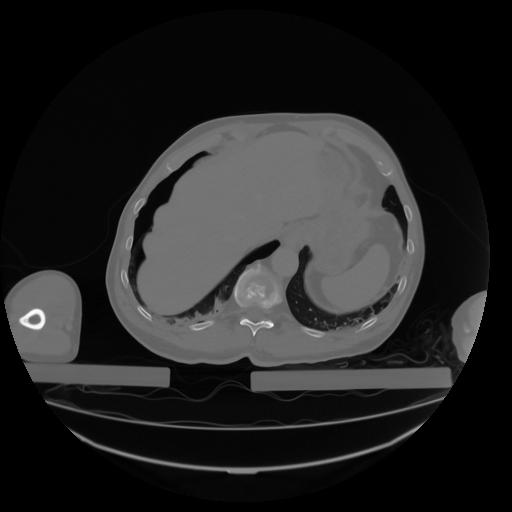

27 CUERPO,CE,Axial,3.0,CUERPO,,